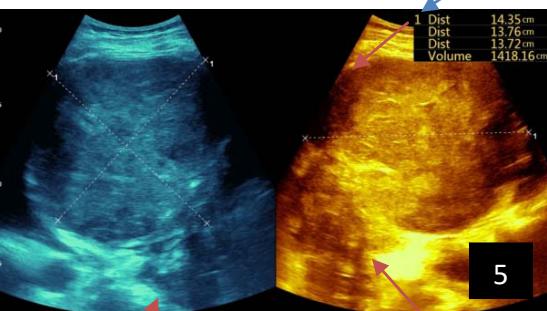

Iconography 1: 54-year-old patient with an intra-splenicsolid mass, anatomopathologically compatible with lymphoma: images 1 and 2: right pleurisy of moderateabundance, image3: celiacadenopathy, image 4: free ascites of moderateabundance, images 5 and 6: intra-splenicsolid mass of around $1418.16\mathrm{ml}$ in B mode and elastographyshowing areas of tumourrigidity, images 7-10: oblique linear images, showingbiopsy gun tracks.